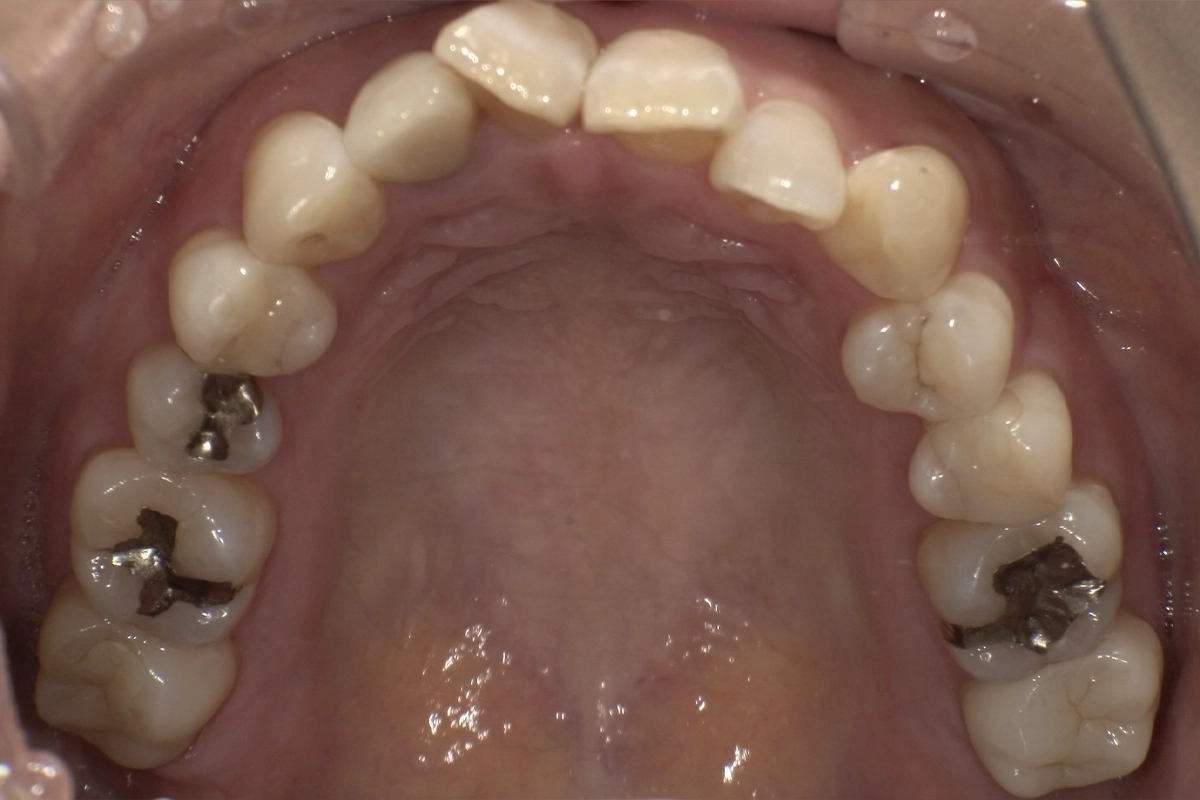

上の前歯にも軽度の乱れがあり、左右の側切歯から犬歯にかけて歯列のアーチが崩れていました。

今回は、上下ともに前から5番目の歯(第二小臼歯)までを対象範囲として治療を行いました。

奥歯(6番目以降の大臼歯)は動かさず、前歯から小臼歯までの範囲に集中してマウスピースで歯を移動させる計画です。